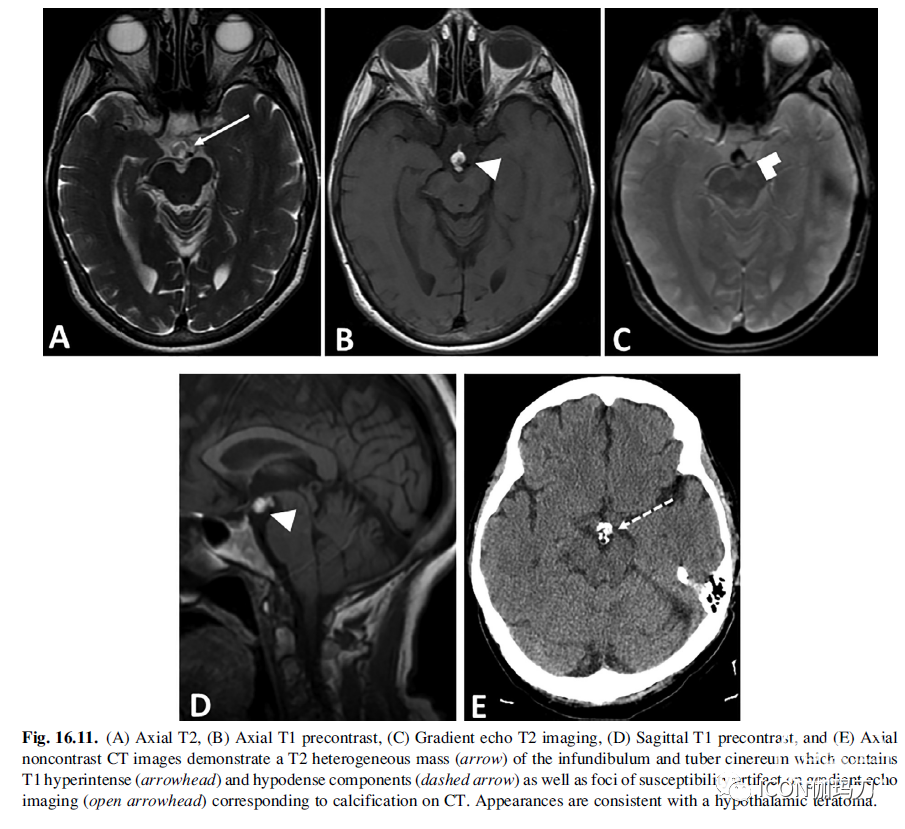

畸胎瘤包含两到三个胚胎层的组织,可以包含多种不同的组织。因此,成像特征是不均匀的。典型的畸胎瘤是囊性和实性混合肿块。MRI是首选的检查方式,尽管CT可以用于评估脂肪和钙化。由于存在囊肿和脂肪,T1信号是从低信号到高信号的变量(图16.11)。软组织成分在T2加权成像上呈等/高信号,并表现出不同程度的增强。在实质性成分中可能存在扩散受限。存在的牙齿成分,脂肪和钙化,高度提示畸胎瘤。临床诊断可先于影像学表现,而影像学表现可能只有在一系列影像学表现中才会随着肿块的生长而变得明显。

图16.11.(A)轴位T2, (B)轴位T1平扫,(C)梯度回波T2成像,(D)矢状位T1平扫,(E)轴位平扫CT示漏斗部和灰结节T2不均匀肿块(箭头),包含T1高(箭头)和低信号成分(虚线箭头),梯度回波成像可见灶性伪影(开箭头),与CT上的钙化相对应。外观符合下丘脑畸胎瘤。